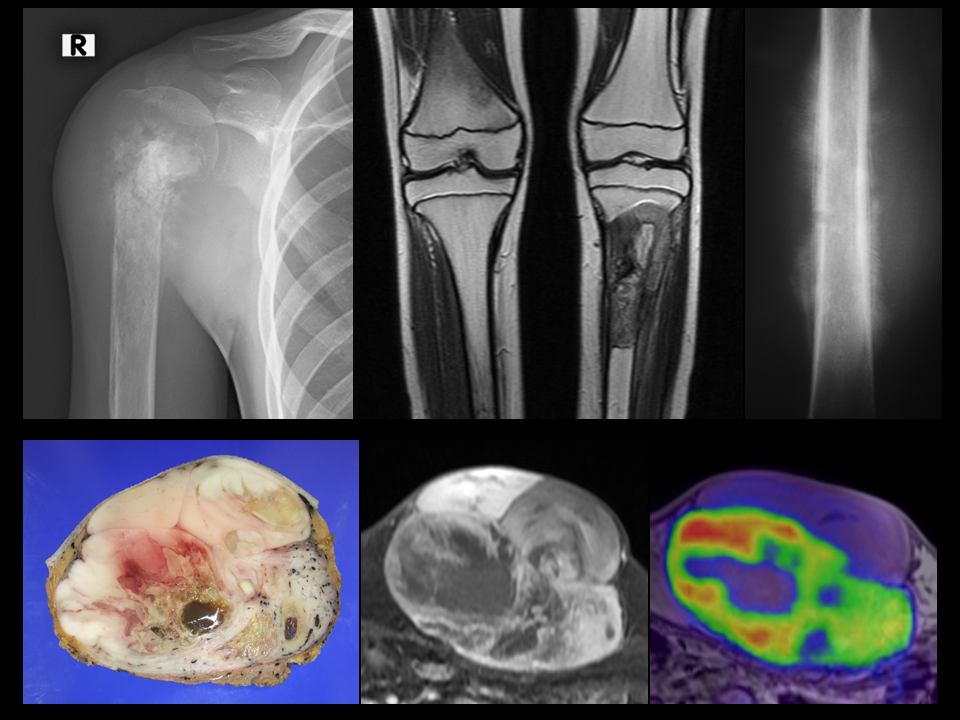

軟部肉腫は、筋肉、脂肪、神経などの軟部組織で発生する希少がんのグループです。体のほぼどの部分でも発症する可能性があります。

この記事では、最も頻繁に診断される種類の軟部肉腫について、その頻度、発生場所、軟部肉腫を患う人の今後の見通しなどを検討します。

軟部肉腫は、体の軟部組織で発生するがんのグループです。最も一般的な 3 つのタイプは次のとおりです。

これらのがんは、それぞれ平滑筋、脂肪細胞、消化管の内側を覆う細胞で発生します。

軟部肉腫患者の見通しはサブタイプによって異なります。脂肪肉腫と滑膜肉腫は、最も悪性度の高いサブタイプの 1 つであると考えられます。